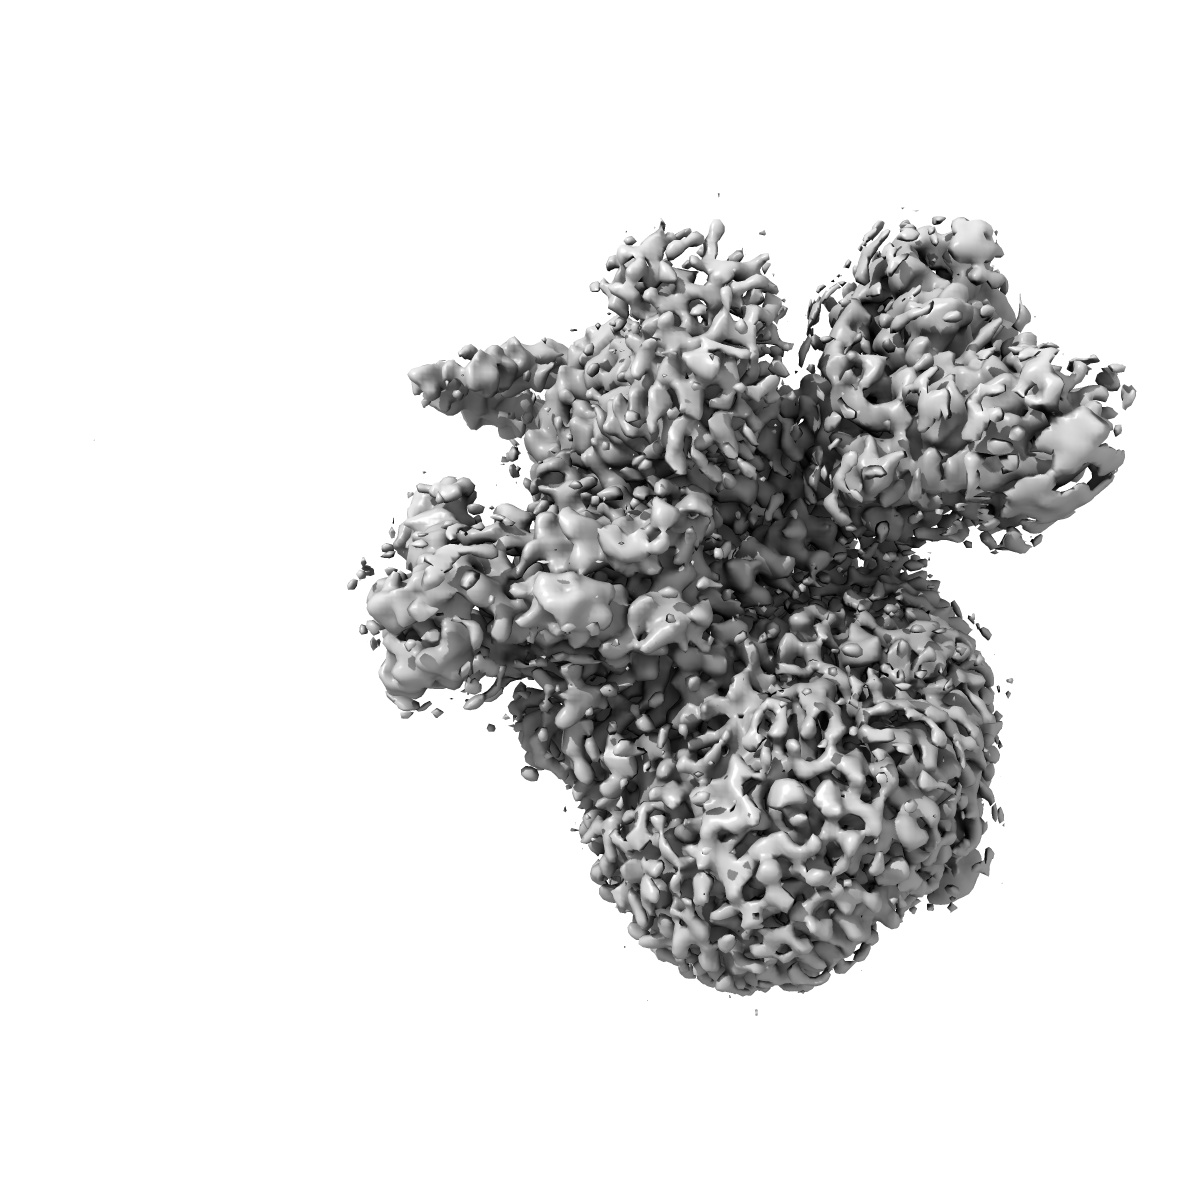

Cryo-EM structure of the alpha2A adrenergic receptor GoA signaling complex bound to a biased agonist

Single-particle3.4 Å

Sample: Signaling complex of alpha2A adrenergic receptor with GoA

Fitted models: 7w7e